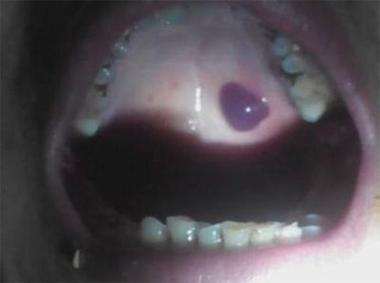

相信不少朋友都有过类似的经历,这个突如其来的“黑色血泡”,医学上通常被称为 “口腔血疱” 或 “黏膜下血肿”,它就像口腔黏膜下的一个小水库,只不过里面装的不是水,而是血管破裂后渗出的血液。

- 外观: 呈现半球形或扁平状,边界清晰,颜色从鲜红、暗红到紫黑色不等,血液越多、越新鲜,颜色可能越偏红;血液被分解后,则可能偏黑。

- 位置: 最常出现在口腔颊黏膜(内腮帮子)、舌腹、软腭等部位,这些地方黏膜较薄,毛细血管丰富,容易受到创伤。